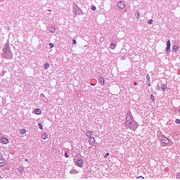

Prion Disease